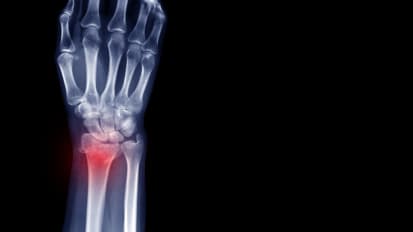

Rethinking Distal Radius Fractures: Evolving Strategies for the Active Osteoporotic Patient

Distal radius fractures remain one of the most common injuries encountered in orthopedic practice.